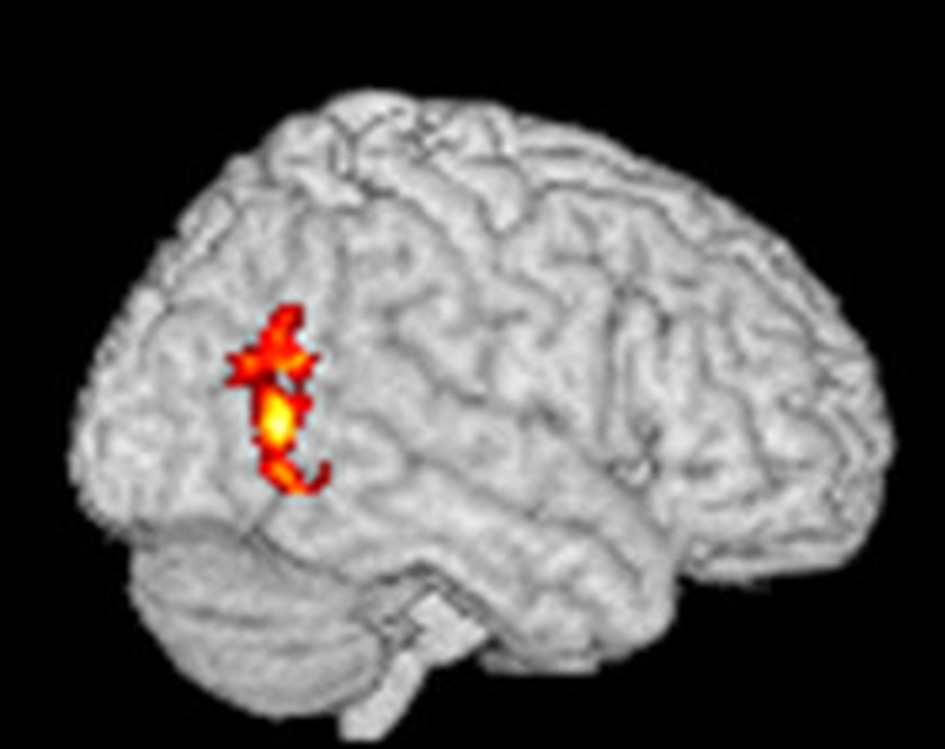

Using an fMRI paradigm designed to measure craving-related brain activity, patients received verbally guided self-generated visualizations of drinking alcohol vs. visualizing non-alcohol scenes during fMRI brain scans before and after four chemical aversion treatments for alcohol use disorder. Compared to pre-treatment, at post-treatment, patients reported significant post-treatment reductions in how much they craved alcohol, and, consistent with our prediction that chemical aversion therapy would reduce craving, their post-treatment fMRI brain scan showed significant reductions in alcohol cue-related brain activity in the occipital cortex (as shown in Figure 4). FMRI statistical images were calculated using FSL's randomize software using the threshold-free cluster enhancement option using a design matrix as shown in this website https://fsl.fmrib.ox.ac.uk/fsl/fslwiki/FEAT/UserGuide#PairedTwo-Group_Difference_.28Two-Sample_Paired_T-Test.29 for paired data. This software does compensate for multiple comparisons and using subject-based permutations to develop the proper statistical distribution to calculate p values. The pre- to post-treatment reduction in alcohol craving related brain activity in the occipital cortex was statistically significant at a corrected p-value < 0.05. Cluster Index = 1, Voxels = 439, p = 0.043, −log10(P) = 1.36, Z-MAX = 3.84, Z-Max X (mm) = 40, Z-Max Y (mm) = −62, Z-MAX Z (mm) = 6, COPE-MAX = 13.2, COPE-MEAN = 7.63. Note that the X, Y, Z coordinates are in MNI space.

Figure 4. Statistical fMRI image showing the areas of brain where there was a significant paired decrease from pre-treatment to post-treatment using verbally cued imagined alcoholic beverage craving stimuli to elicit craving-related brain activation before and after aversive conditioning. The red areas show where there was a significant change in fMRI at a corrected p-value < 0.05 and the yellow areas show where there was a significant change in fMRI at a corrected p-value < 0.03.